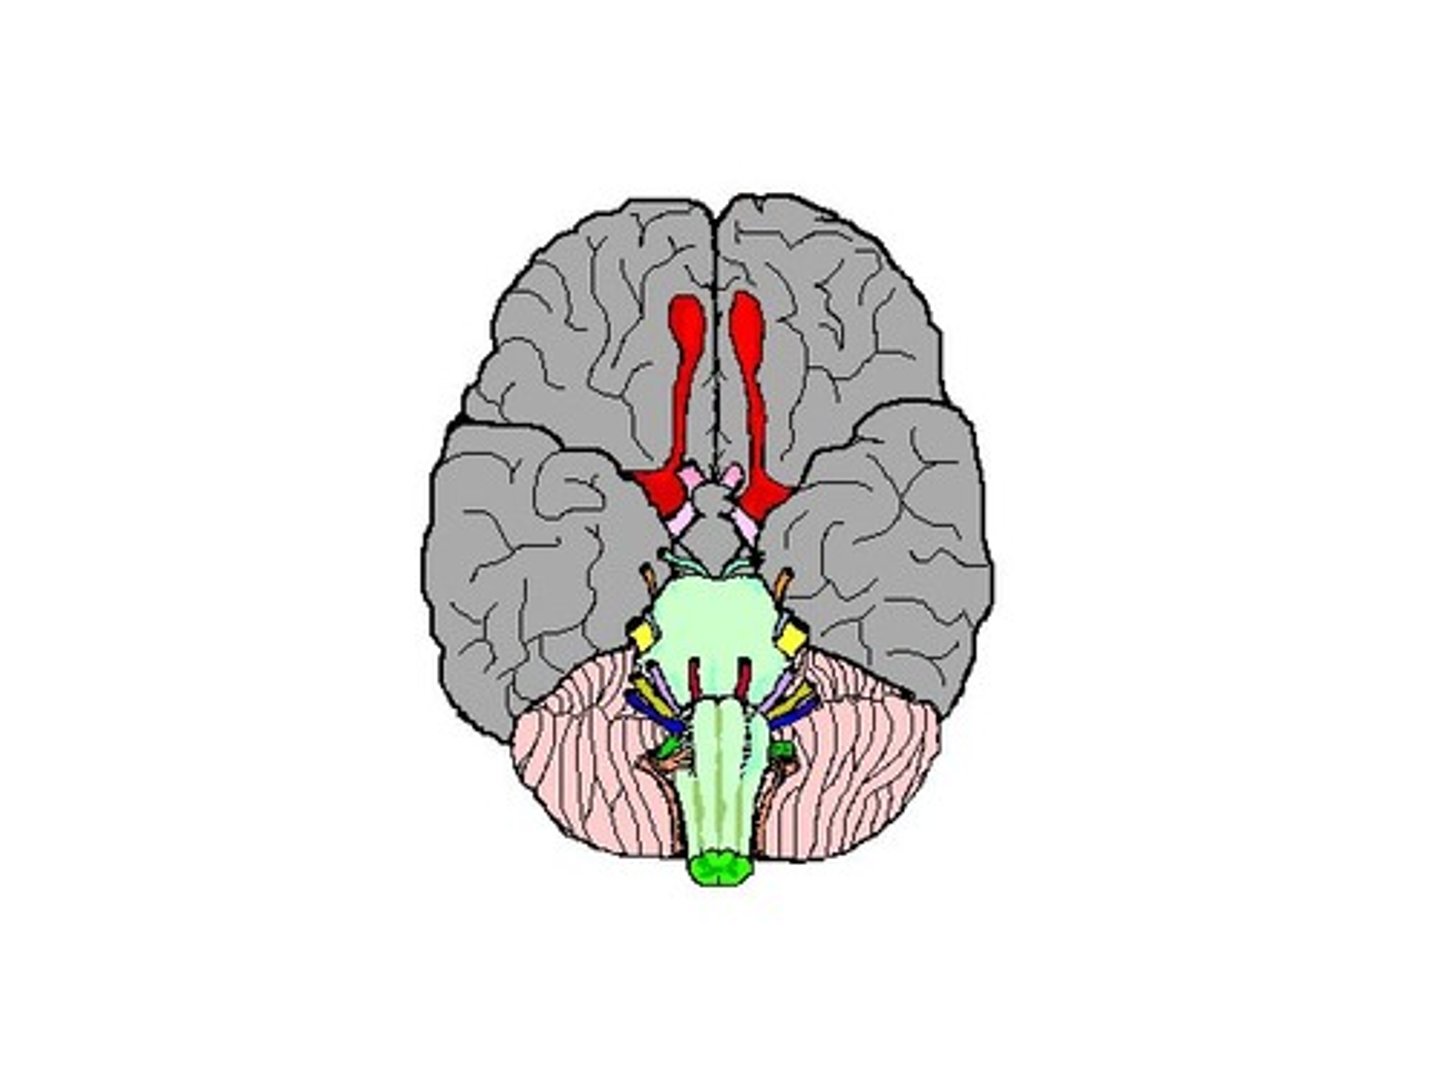

Cranial Nerves

Olfactory (S) smell

Optic (S) vision

Oculomotor (M): pupil dilation

Trochlear(M) eye movement

Trigeminal (B) sensory and motor control of face

Abducens (M): eye movement

Facial (B) facial movement

Vestibulocochlear (S) hearing and balance

Glossopharyngeal (B): control of muscles used for swallowing

Vagus (B): stimulation of the diaphragm

Accessory spinal (M): control muscle movement of head

Hypoglossal (M): control of the tongue

Cranial Nerve 1 or olfactory bulb

neural structure of the vertebrate forebrain involved in olfaction, or the sense of smell. Flow of olfactory information from receptors to glomeruli layer

Cranial Nerve 2 or optic nerve

each of the second pair of cranial nerves, transmitting impulses to the brain from the retina at the back of the eye.

Optic Chiasma

the X-shaped structure formed at the point below the brain where the two optic nerves cross over each other